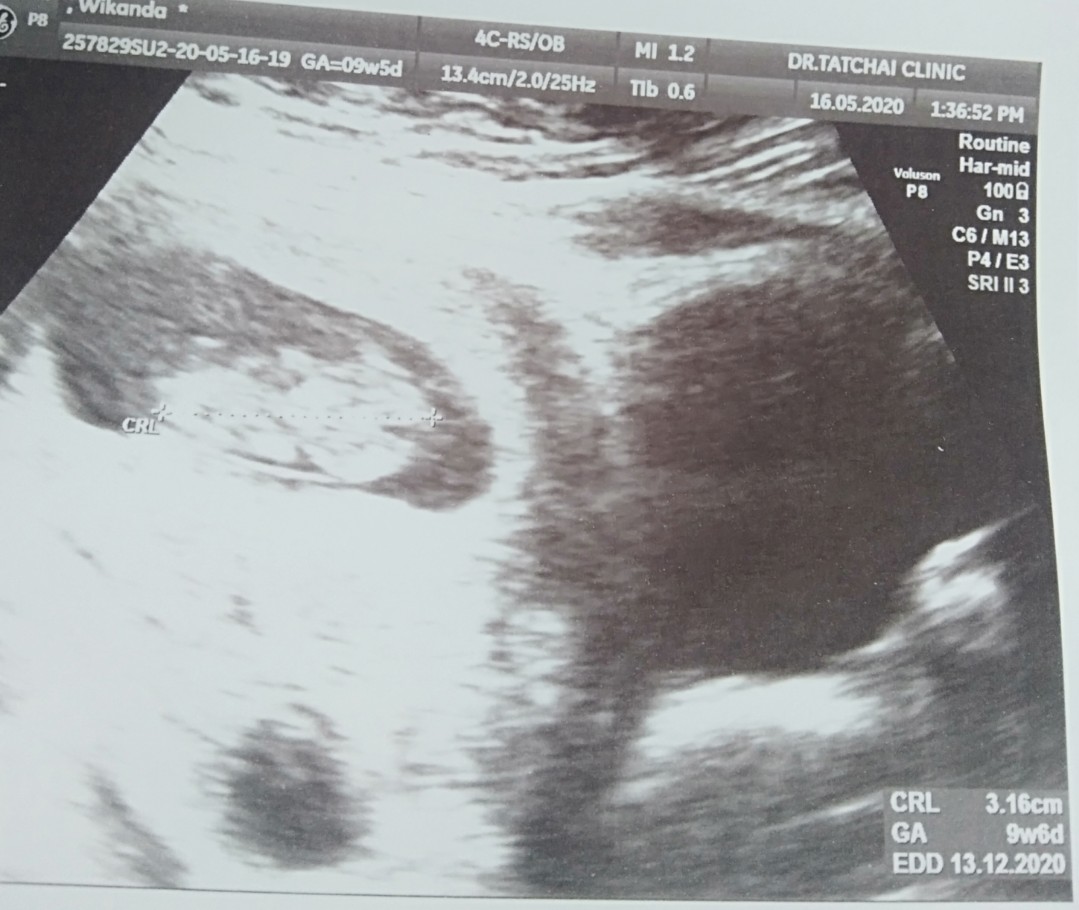

13 /12/63 ค่ะ

13/12/20